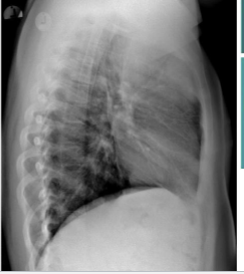

What is this? and what causes it?

air space filling w air bronchograms, PNA